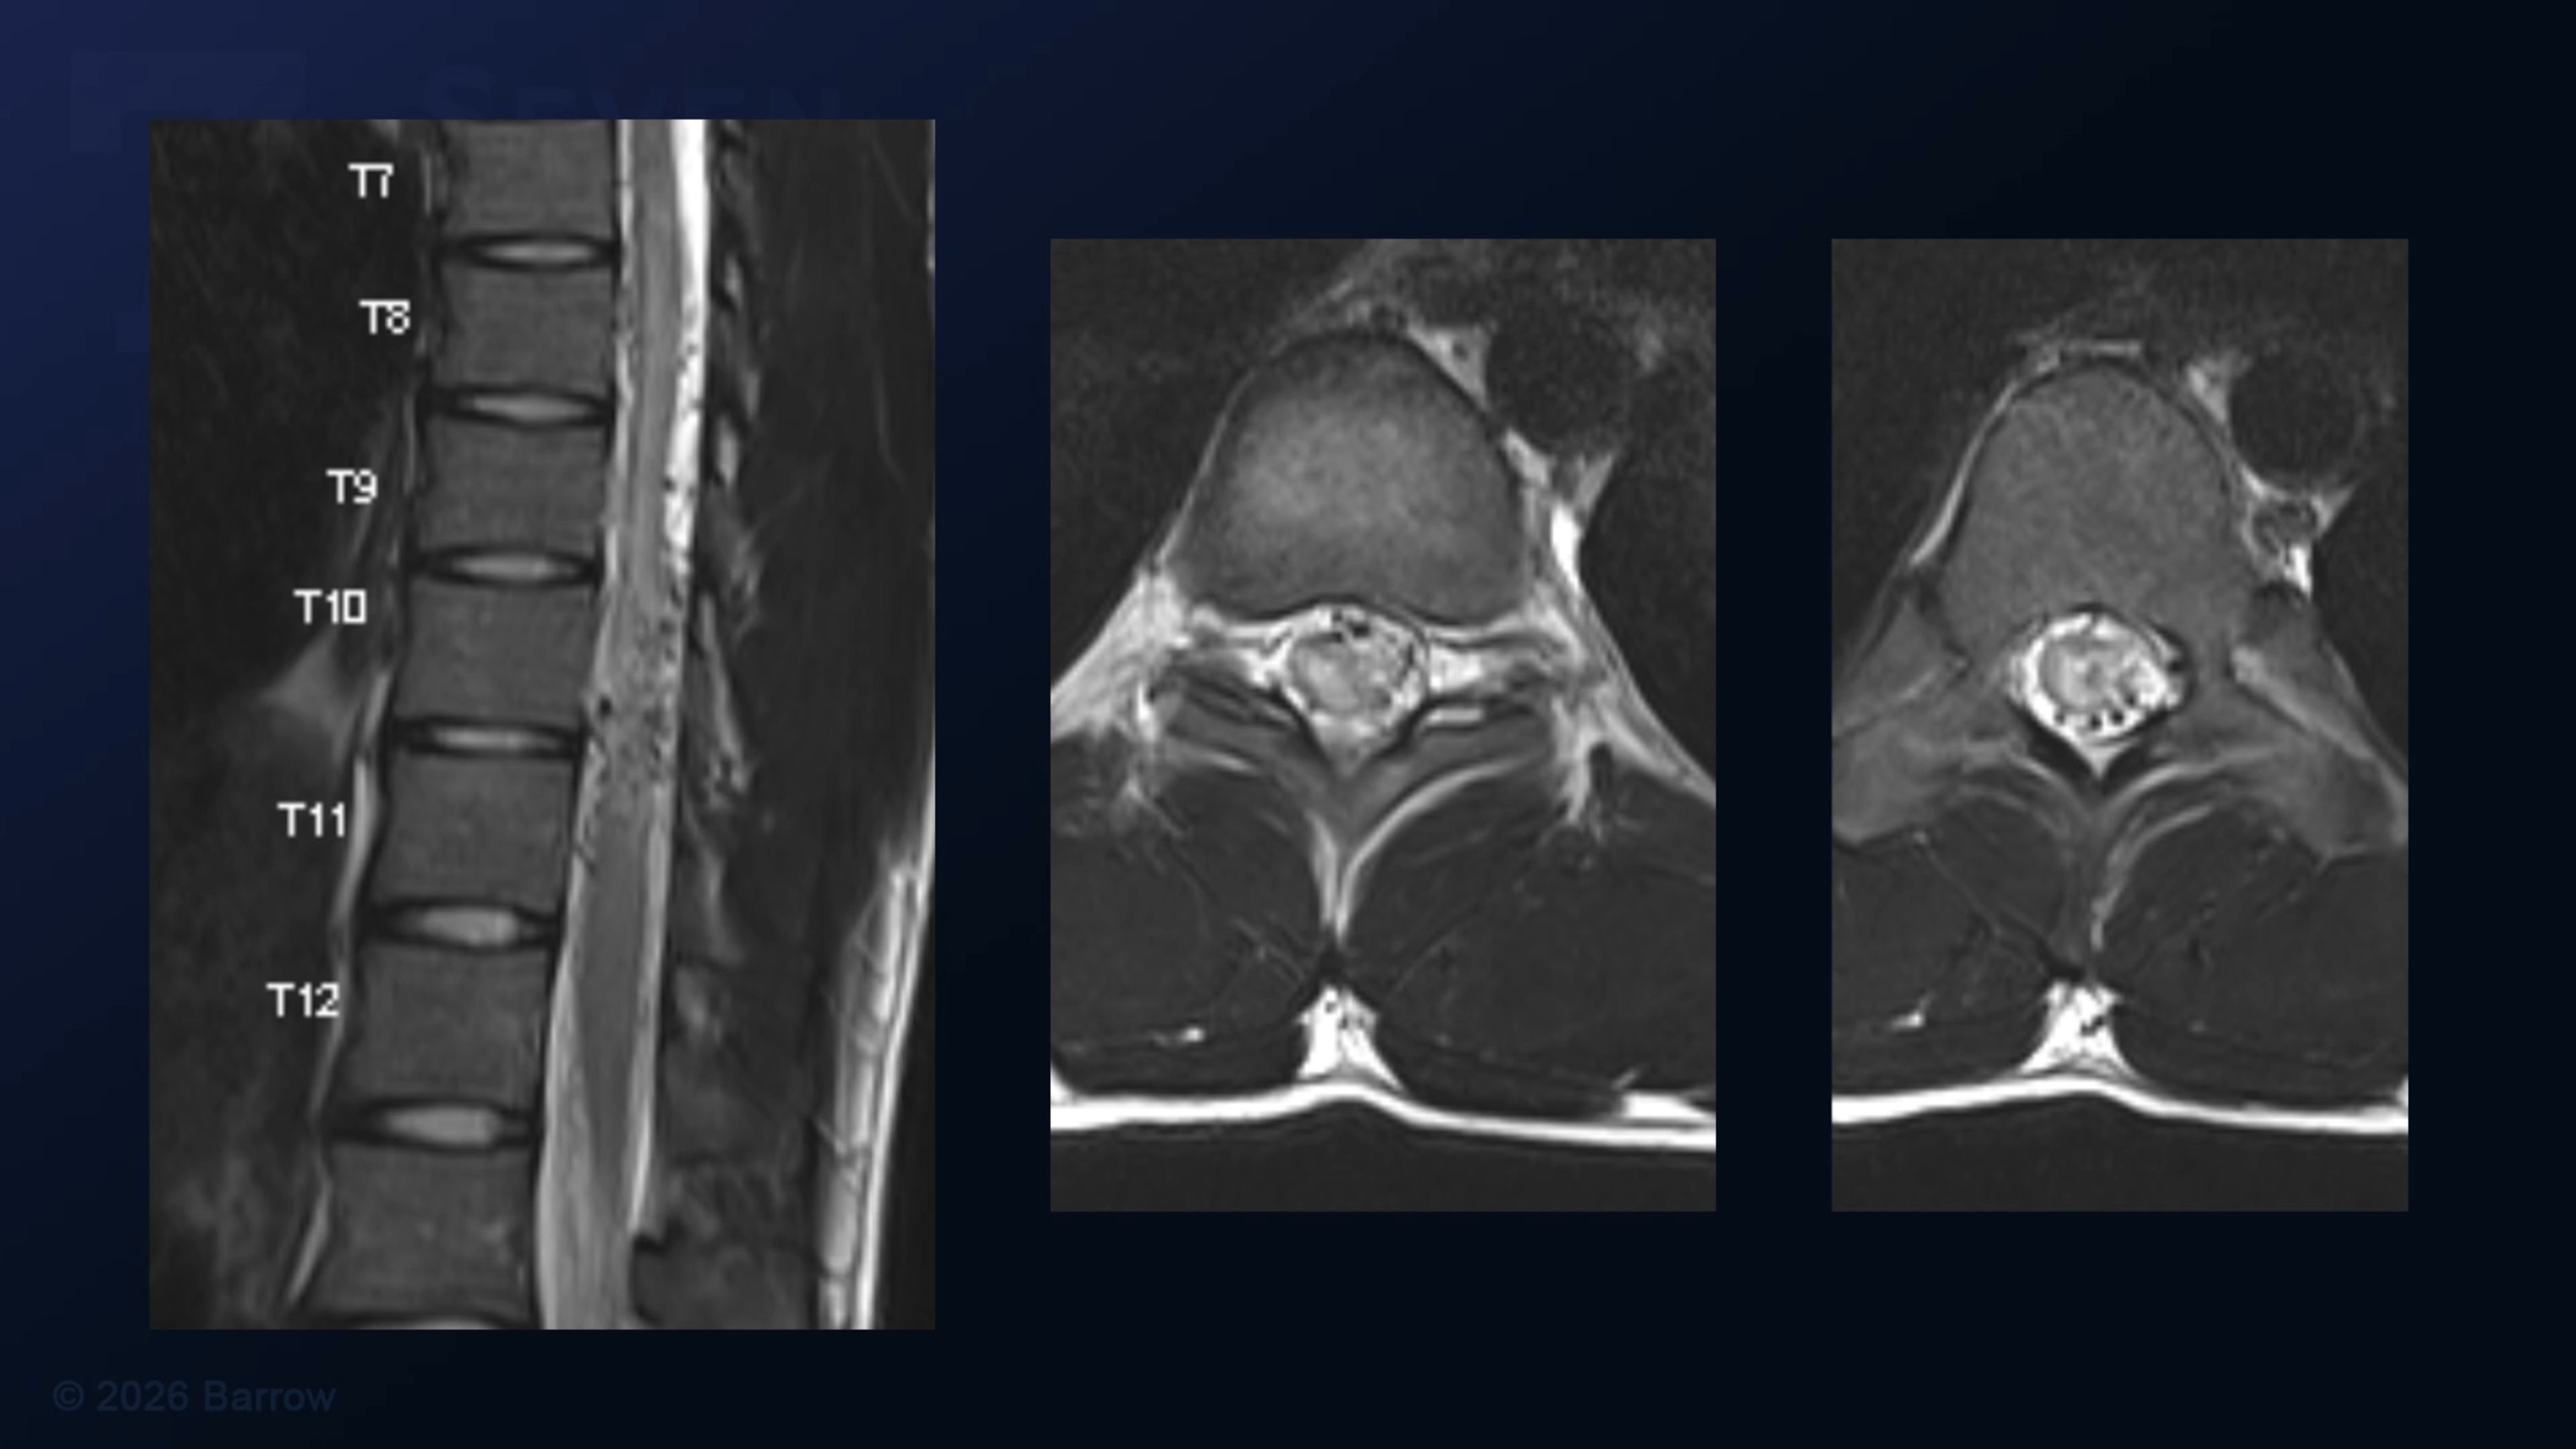

Episode 525 of Seven Series shows a T9-T11 laminectomy with left T10 costotransversectomy for resection of an eccentric intramedullary spinal cord arteriovenous malformation.